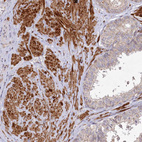

Immunohistochemical staining of human Testis shows strong granular cytoplasmic positivity in Leydig cells.